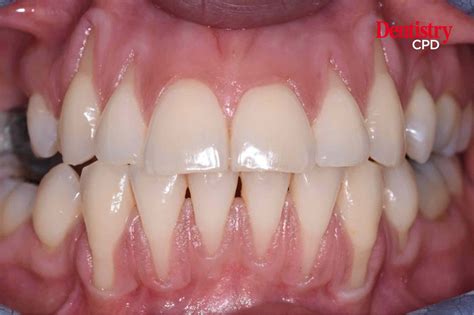

Have you ever noticed your teeth looking slightly longer than usual, or perhaps felt a sudden, sharp sensitivity when consuming a hot cup of coffee or a cold scoop of ice cream? If so, you might be experiencing a common dental condition known as the recession of gingiva. Often referred to simply as gum recession, this process involves the gum tissue surrounding the teeth pulling away, wearing down, or pulling back, thereby exposing more of the tooth or its root. While it might seem like a minor cosmetic issue, it is a significant dental concern that, if left unaddressed, can lead to serious oral health complications, including tooth decay and even tooth loss.

Identifying the Signs and Symptoms

Because the recession of gingiva often occurs slowly, many people do not notice it until the symptoms become obvious. Being proactive is essential for early detection. Watch out for the following warning signs:

• Increased sensitivity to hot, cold, or sweet foods and drinks.

• Teeth that appear longer than before.

• Visible roots of the teeth.